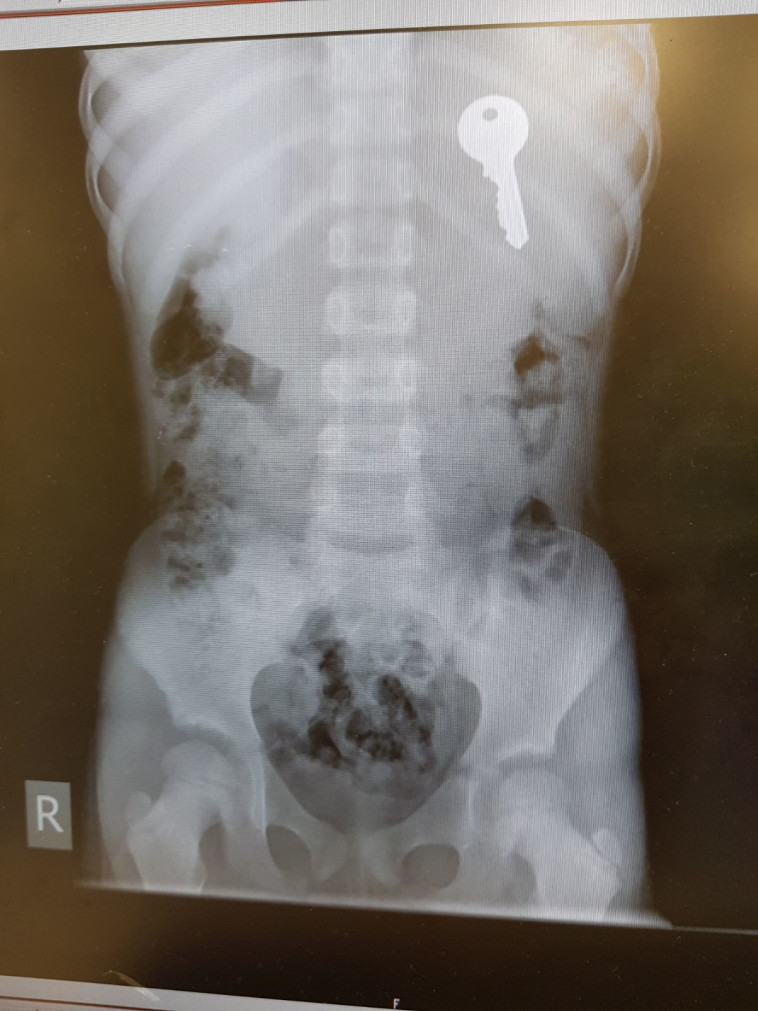

באירוע אחר בדרום, ילדה בת 6 בלעה מפתח, הובהלה למיון 'טרם' באשקלון, שם הוא נמצא והוצא מגופה.

מפתח שנמצא בגופה של בת 6. צילום: דוברות טרם

מפתח שנמצא בגופה של בת 6. צילום: דוברות טרם | מפתח שנמצא בגופה של בת 6. צילום: דוברות טרם